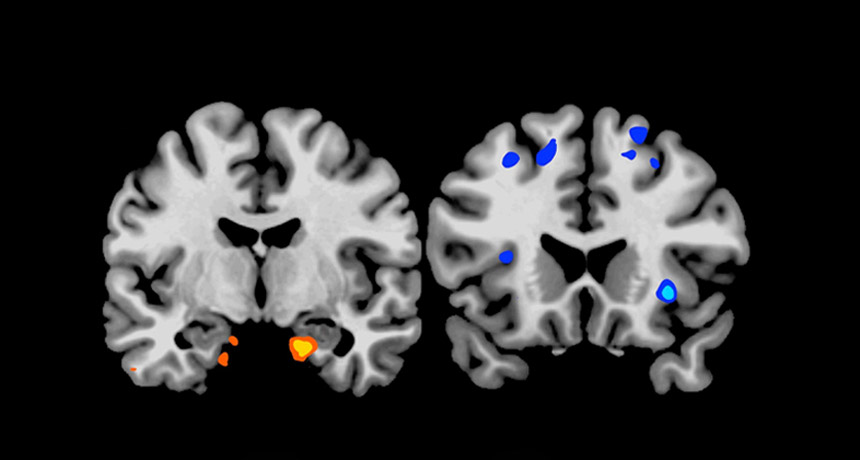

MMM, DOUGHNUTS  When confronted with a picture of junk food, people who pulled all-nighters had boosted activity in the amygdala (left), a brain structure associated with the desire to eat, and reduced activity in regions of  the cortex (right), which have been tied to food evaluation.

Matthew Walker et al.